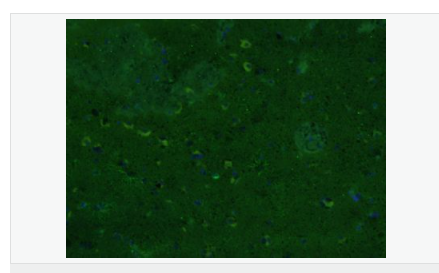

| 產(chǎn)品應用 | WB=1:500-2000 ELISA=1:5000-10000 IHC-P=1:200-1000 IHC-F=1:200-1000 Flow-Cyt=1μg/Test ICC=1:100 IF=1:200-800 (石蠟切片需做抗原修復) not yet tested in other applications. optimal dilutions/concentrations should be determined by the end user. |

| 產(chǎn)品介紹 | This gene encodes one of the major intermediate filament proteins of mature astrocytes. It is used as a marker to distinguish astrocytes from other glial cells during development. Mutations in this gene cause Alexander disease, a rare disorder of astrocytes in the central nervous system. Alternative splicing results in multiple transcript variants encoding distinct isoforms. [provided by RefSeq, Oct 2008] Function: GFAP, a class-III intermediate filament, is a cell-specific marker that, during the development of the central nervous system, distinguishes astrocytes from other glial cells. Subunit: Interacts with SYNM. Isoform 3 interacts with PSEN1 (via N-terminus). Subcellular Location: Cytoplasm. Note=Associated with intermediate filaments. Tissue Specificity: Expressed in cells lacking fibronectin. Post-translational modifications: Phosphorylated by PKN1. DISEASE: Defects in GFAP are a cause of Alexander disease (ALEXD) [MIM:203450]. Alexander disease is a rare disorder of the central nervous system. It is a progressive leukoencephalopathy whose hallmark is the widespread accumulation of Rosenthal fibers which are cytoplasmic inclusions in astrocytes. The most common form affects infants and young children, and is characterized by progressive failure of central myelination, usually leading to death usually within the first decade. Infants with Alexander disease develop a leukoencephalopathy with macrocephaly, seizures, and psychomotor retardation. Patients with juvenile or adult forms typically experience ataxia, bulbar signs and spasticity, and a more slowly progressive course. Similarity: Belongs to the intermediate filament family. SWISS: P14136 Gene ID: 2670 Database links: Entrez Gene: 2670 Human Entrez Gene: 14580 Mouse Omim: 137780 Human SwissProt: P14136 Human SwissProt: P03995 Mouse Important Note: This product as supplied is intended for research use only, not for use in human, therapeutic or diagnostic applications. 星形膠質細胞標志物 (Astrocyte Marker) GFAP是一個56kDa的中間絲蛋白(intermediate filament,IF),在中樞神經(jīng)系統(tǒng)發(fā)育期是一個特異性的標志物,以區(qū)別星形細胞和其它膠質細胞。GFAP表達在皮層和海馬,急、慢性皮質酮治療時表達減少。 GFAP可以和人、大鼠、小鼠的GFAP反應,在正常和腫瘤性的星形膠質細胞陽性表達,而神經(jīng)節(jié)細胞、神經(jīng)元、成纖維細胞、少突膠質細胞和這些細胞來源的腫瘤細胞陰性表達,主要用于星形膠質瘤等中樞神經(jīng)系統(tǒng)腫瘤的診斷和鑒別診斷,GFAP的缺乏可導致AD病。 |